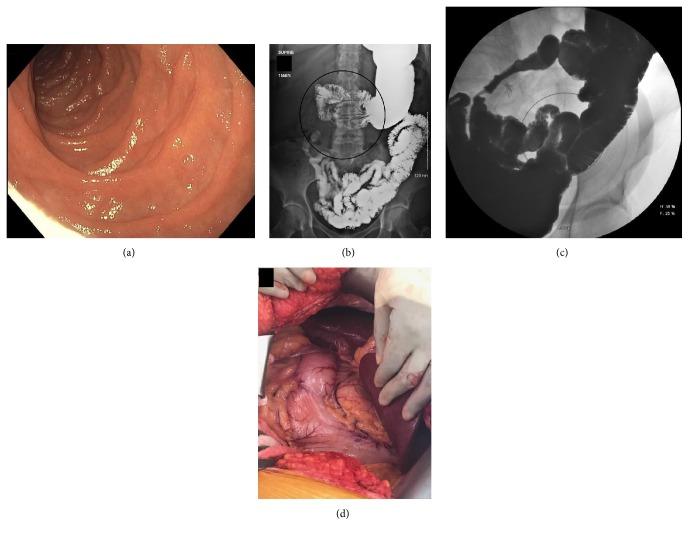

Duodenum inversum (DI), also known as inverted duodenum or duodenum reflexum, is a congenital malformation in which the third portion of the duodenum, instead of continuing leftward to the ligament of Treitz, reverses direction and travels in a superior, posterior track prior to crossing the midline above the pancreas. We present a case of a 62-year-old woman presenting with chronic nausea and vomiting, subsequently found to have DI.

十二指肠反向(DI),也称为十二指肠倒置或十二指肠反位,是一种先天性畸形,其中十二指肠第三部不是向左延续至Treitz韧带,而是改变方向,在越过胰腺上方的中线之前沿向上、向后的路径走行。我们报告一例62岁女性,表现为慢性恶心和呕吐,随后被发现患有十二指肠反向。